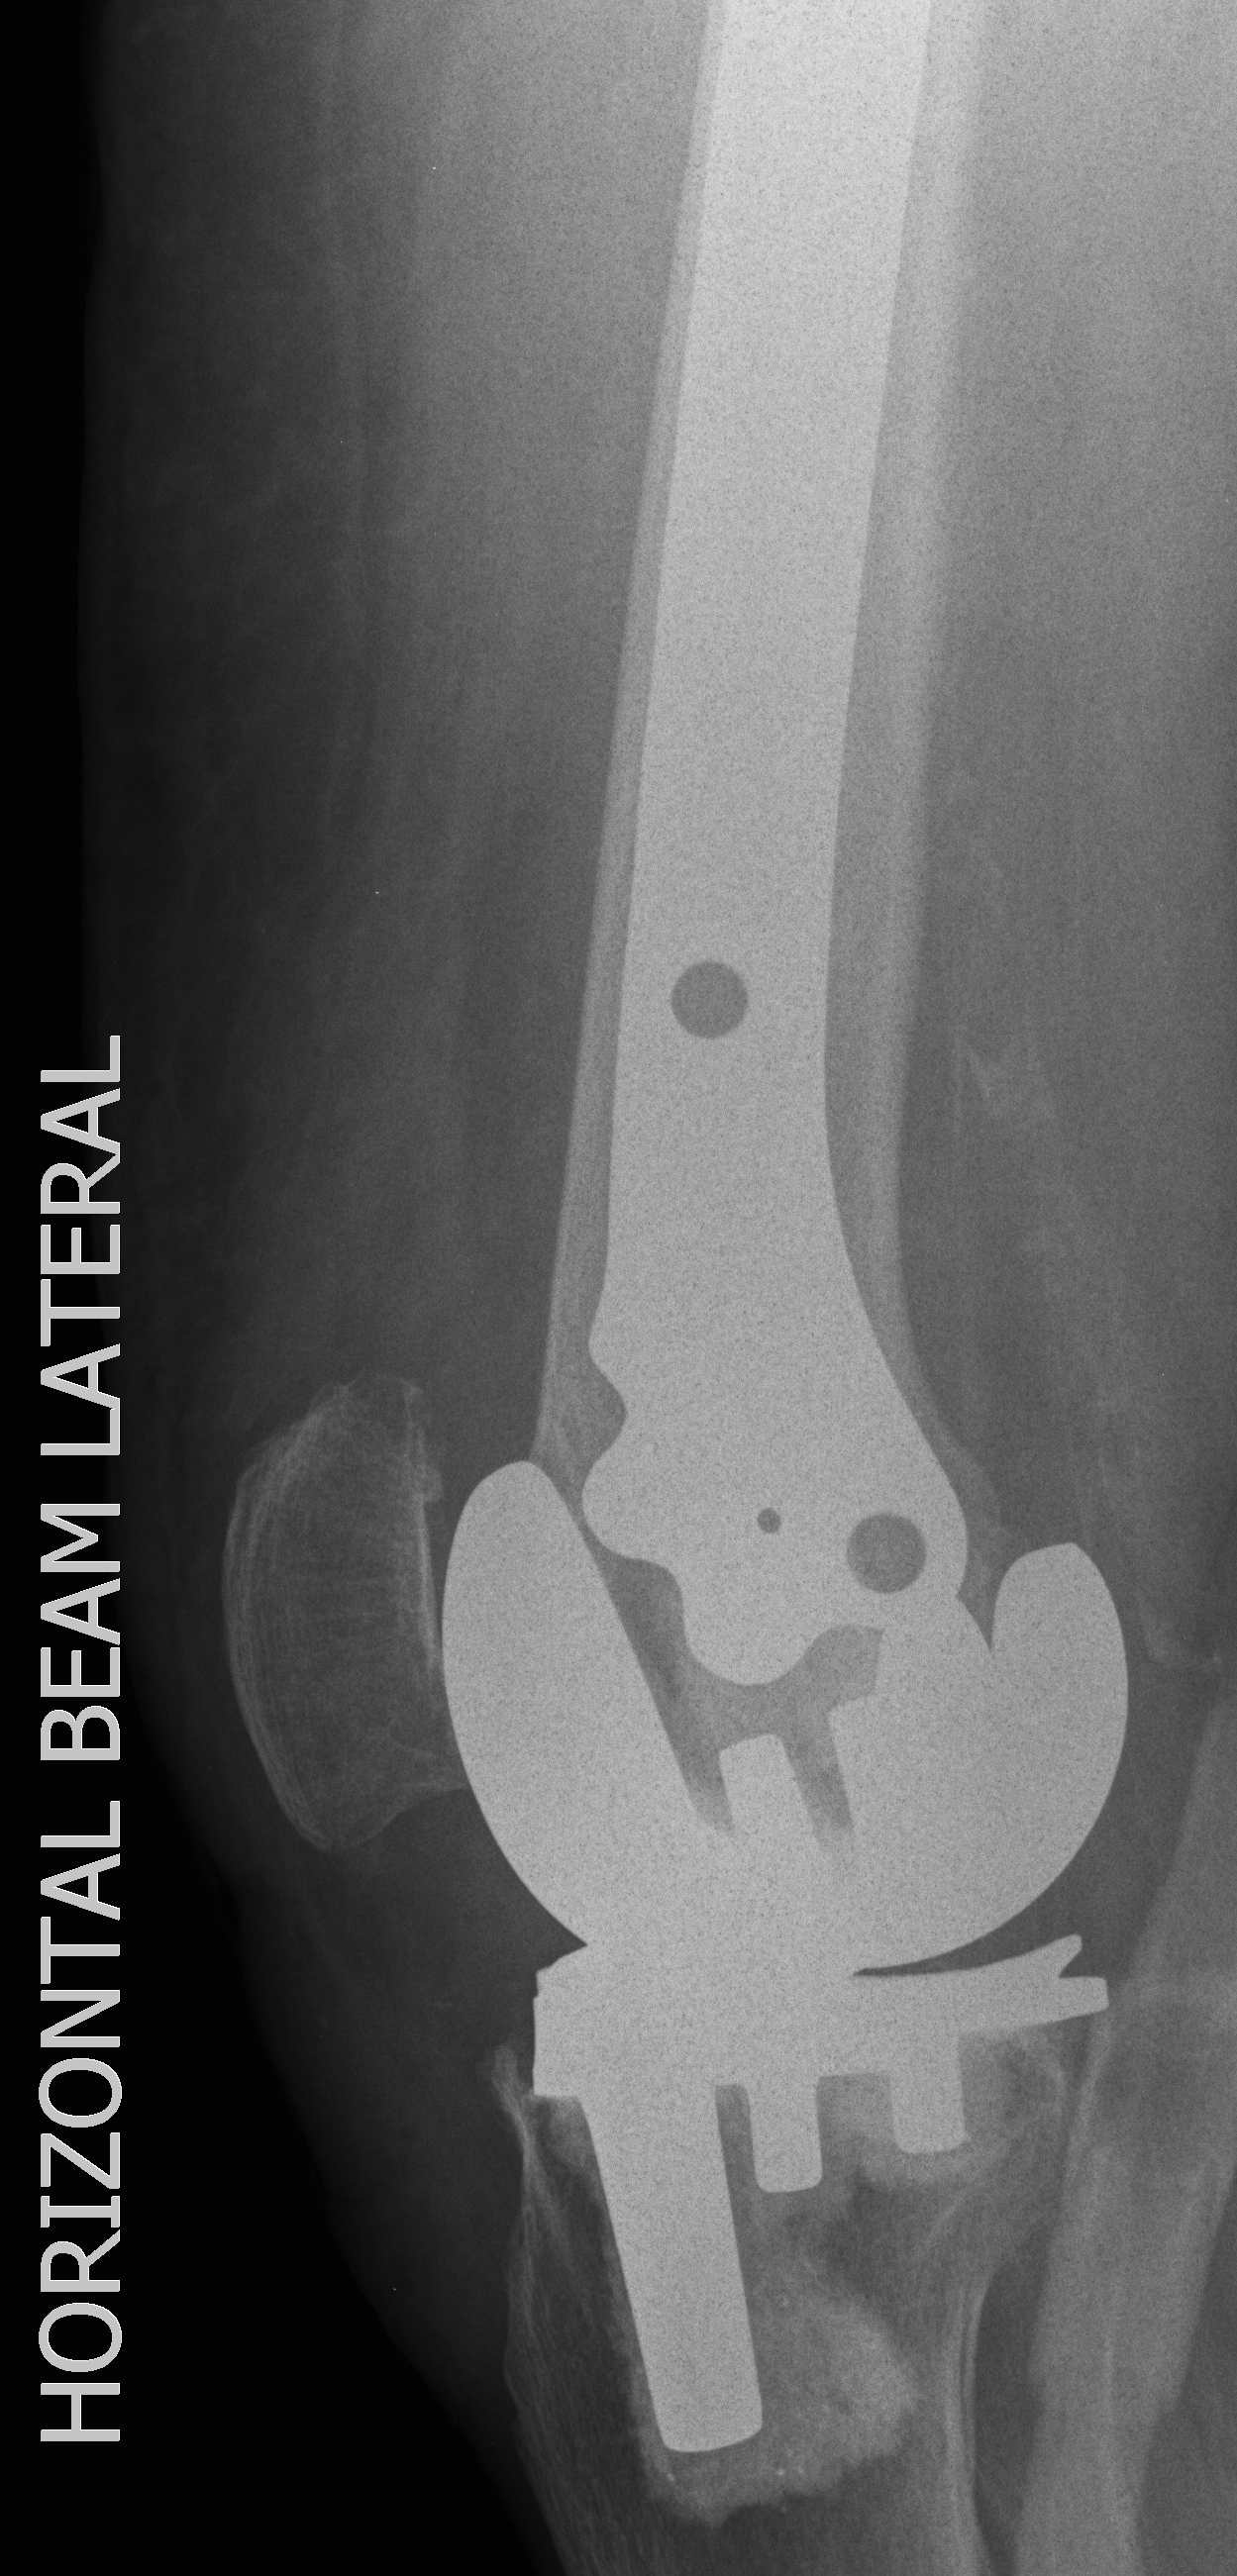

4.  Revision TKR

Indications

- very distal fracture

- insufficient bone stock

- loose prosthesis

Components

- stemmed, constrained implant

- tumour prosthesis

TKR Periprosthetic Fracture APTKR Periprosthetic Fracture LateralTKR Periprosthetic Fracture Revision APTKR Periprosthetic Fracture Revision Lateral